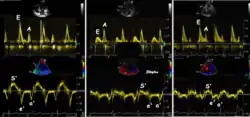

During the two filling phases, there is early (E) and late (A) blood flow from the atrium to the ventricle, corresponding to the annular velocity phases. The flow, is driven by the pressure difference between atrium and ventricle, this pressure difference is both a function of the pressure drop during early relaxation and the initial atrial pressure. In light diastolic dysfunction, the peak early mitral flow velocity E is reduced in proportion to the e', but if relaxation is so reduced that it causes increase in atrial pressure, E will increase again, while e', being less load dependent, remains low. Thus, the ratio E/e' is related to the atrial pressure, and can show increased filling pressure[15][16] although with several reservations.[17][18] In the right ventricle this is not an important principle, as the right atrial pressure is the same as central venous pressure which can easily be assessed from venous congestion.[19][20]

relation between mitral flow and mitral annulus velocity. Left: Normal person with good diastolic function; high E and e', normal E/e'. Middle, patient with diastolic dysfunction without increased filling pressure; low E and e', normal E/e' ratio. Left, patient with diastolic dysfunction and increased filling pressure; high E, low e' and high E/e'. The S' is reduced in proportion to the e'